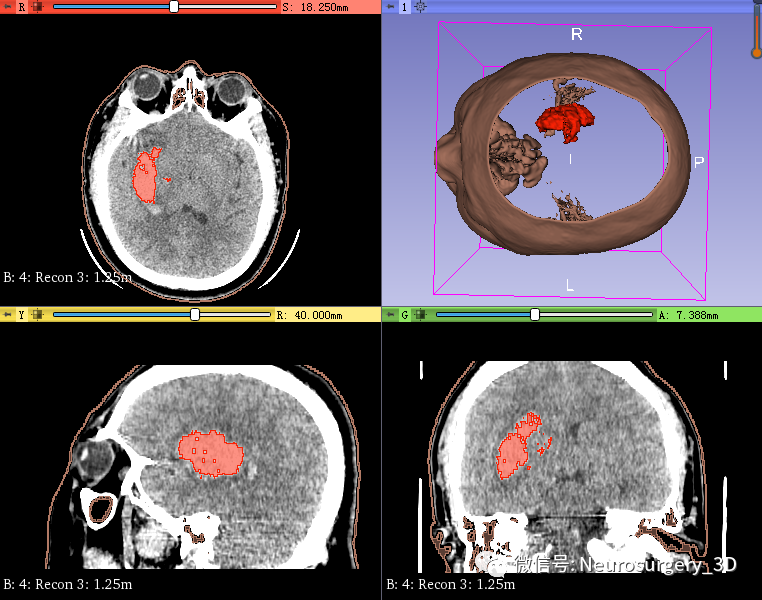

1、同阈值分割法建立血肿,应用阈值分割法三维重建头颅原始模型

2、可透视化显示颅内血肿形态

3、利用Logical operators逻辑运算模块复制头颅原始模型并扩大。

4、再次利用Logical operators逻辑运算模块,运算后重建出面具三维模型

运算后结果